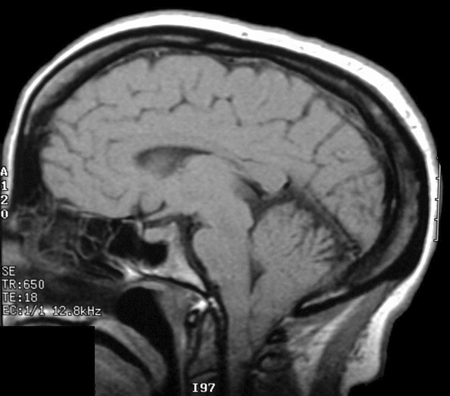

Ressonância nuclear magnética (RNM) cranioencefálica mostrando malformação de Chiari

Do acervo do Dr. Nienke P. Dosa; usado com permissão